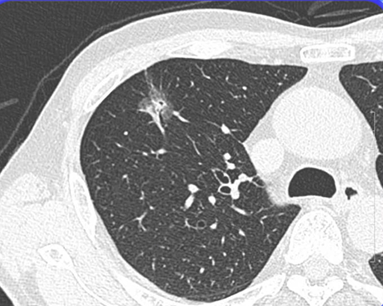

■CT像

精査の結果「初期の肺腺癌」でした。このように読影能力次第で患者さんの寿命を大きく左右してしまうことが多いのが肺癌ですので、普段からの研鑽が大事になります。